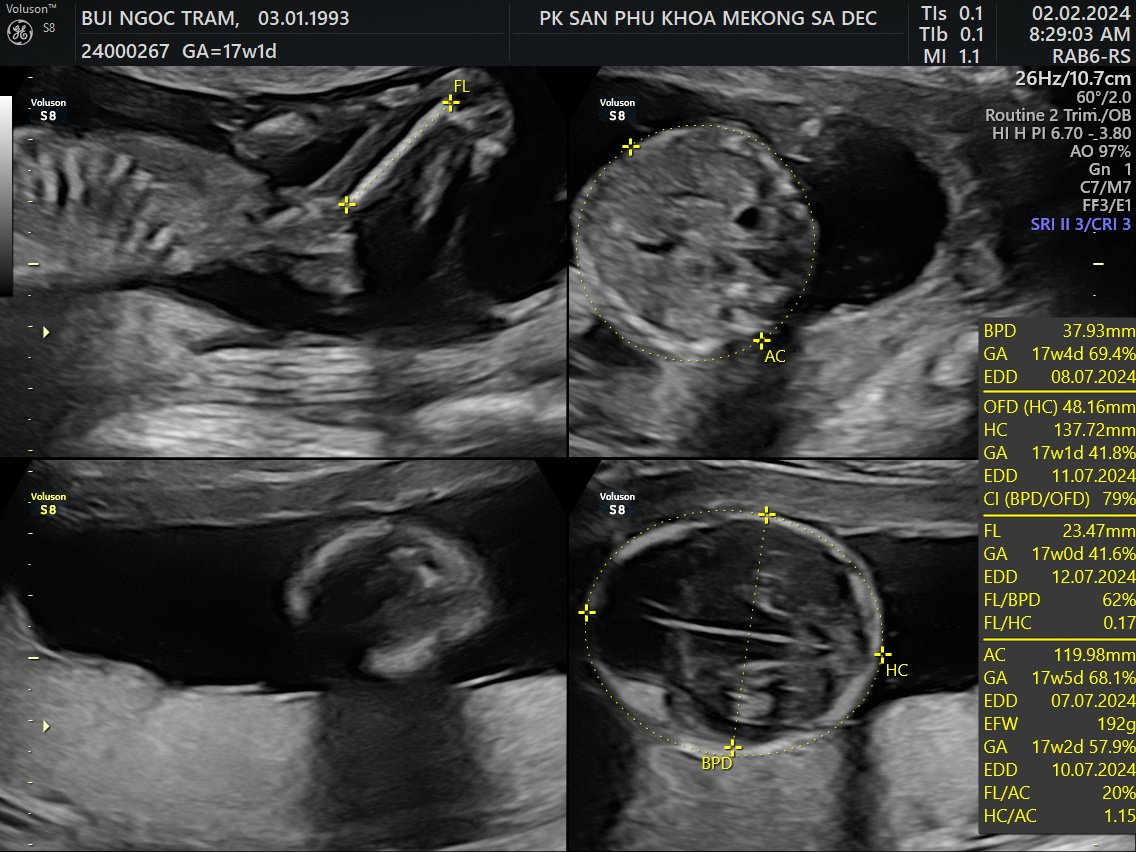

Siêu âm 5D

Tuần 17

2 Feb 2024

Về Sadec, được đi siêu âm 5DLà con trai, hơi ú và hành mẹ bị viêm bạch huyết, hên là phát hiện sớm và được bác sĩ cho thuốc!